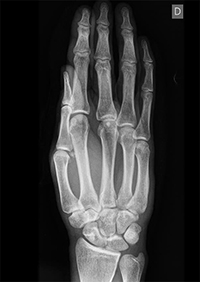

Las lesiones por arma blanca son muy lesivas aunque la afectación cutánea pueda ser escasa y la radiología, como podéis ver, difícil de valorar.